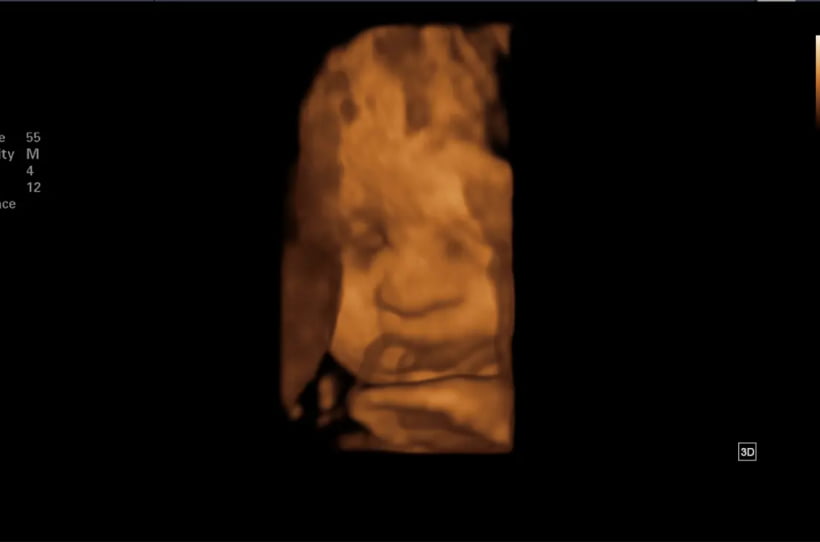

Ecografía Obstétrica 3D

¿Sueña con conocer a su bebé antes del parto? Ahora en Udimágenes contamos con la tecnología de punta que permiten hacer realidad el sueño de ver al bebé en vivo con una claridad excepcional mientras esta en el vientre. Disfrute de imágenes y videos en alta resolución que capturan cada detalle, brindándole una experiencia única en el embarazo. Venga y experimente este hermoso momento para conocer a su pequeño antes de su llegada.